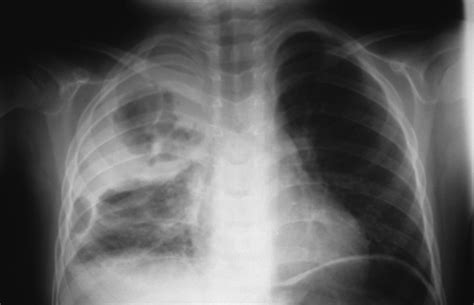

Pneumonia is an infection that inflames the air sacs (alveoli) in one or both lungs. When these air sacs fill with fluid or pus, they appear denser than the surrounding healthy air-filled lung tissue on an X-ray. Radiologists look for specific patterns of opacity, often referred to as infiltrates or consolidations, to confirm a diagnosis of pneumonia on CXR.

• Lobar Consolidation: This is the classic appearance of bacterial pneumonia, such as that caused by Streptococcus pneumoniae. A defined portion of a lung lobe appears white (opaque) due to the consolidation of fluid, often featuring air bronchograms—dark, branching lines representing air-filled bronchi surrounded by consolidated alveoli.